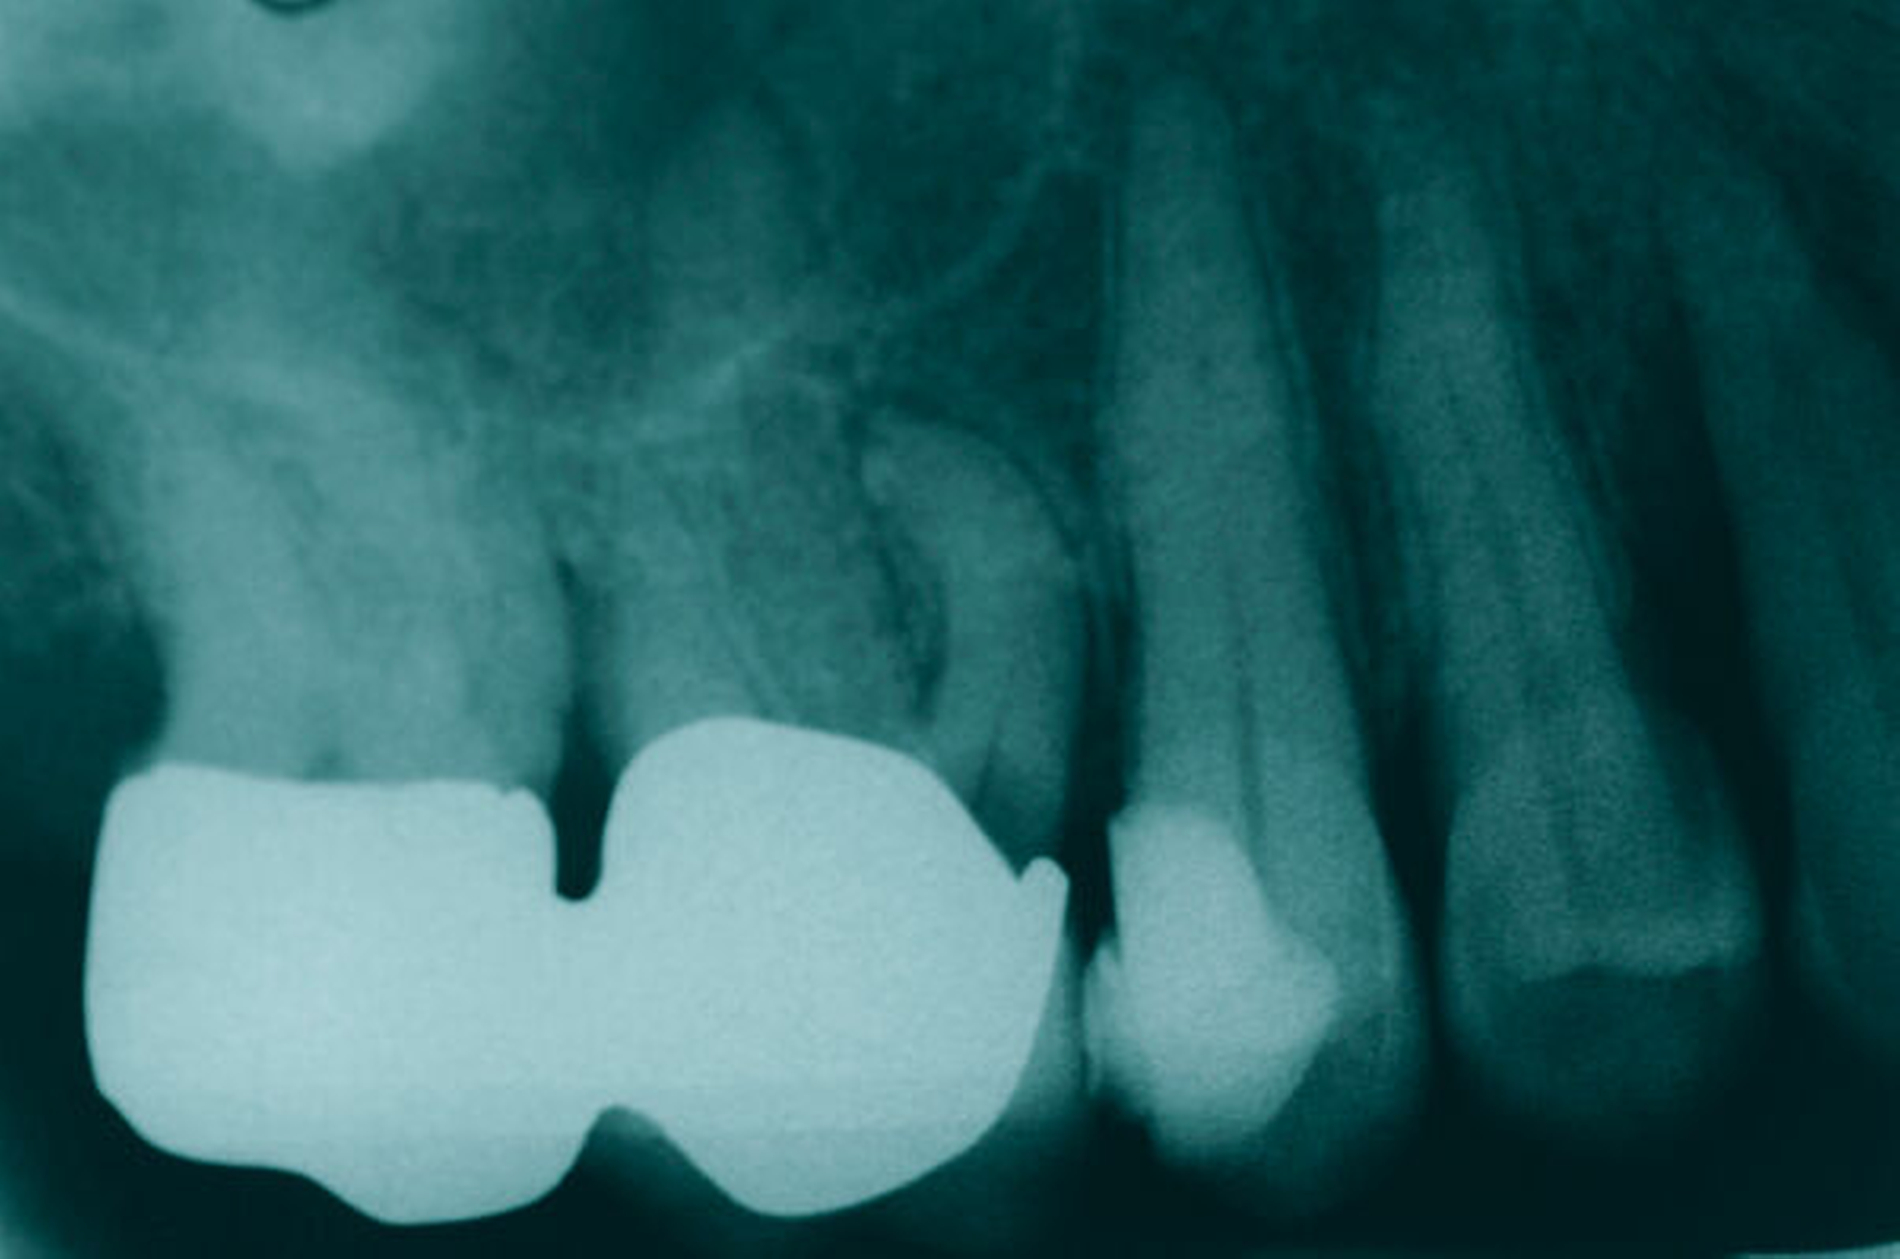

Ein 59-jähriger Patient stellte sich erstmals 2015 mit rezidivierenden pochenden Beschwerden und zeitweise zusätzlich auftretendem Pusaustritt an Zahn 16 vor. Klinisch zeigte sich ein ausgeprägter Attachmentverlust distal mit bis apikal sondierbarer distobukkaler Wurzel, Furkationsbeteiligung und Pusaustritt sowohl über den Parodontalspalt als auch durch einen distobukkal gelegenen Fistelausgang. Zunächst erfolgte die endodontische Behandlung des Zahnes 16 mit anschließender systematischer PA-Therapie. Bei persistierender parodontaler Problematik an 16 wurde die Möglichkeit der Teilamputation der distobukkalen Wurzel mit dem Patienten diskutiert, um die Hygienefähigkeit und damit die Prognose des Zahnes zu verbessern. Auch über die Extraktion als Alternative wurde der Patient aufgeklärt. Er war allerdings motiviert, seinen Zahn so lange wie möglich zu erhalten.

So erfolgte die Amputation der distobukkalen Wurzel mit anschließender Versorgung des Zahnes mittels Vollkrone. Die Situation an 16 ist seitdem für den Patienten subjektiv stabil, die aktuelle Röntgenkontrolle zeigt jedoch eine Progredienz der parodontalen Defekte trotz regelmäßiger UPT und subjektiv guter Mitarbeit des Patienten, was die Prognose des Zahnes negativ beeinflusst. Ursächlich hierfür kann eine persistierende parodontale Infektion durch den trotz Wurzelamputation immer noch schwer für die häusliche Mundhygiene zugänglichen Furkationsbereich mit enger Lagebeziehung der mesiobukkalen und der palatinalen Wurzel sein. Der Patient ist allerdings aktuell mit der Situation zufrieden und beschwerdefrei und wünscht daher noch keine Extraktion des Zahnes, auch wenn diese sich nun fünf Jahre nach dem initialen Befund nicht mehr sehr lange vermeiden lassen wird.